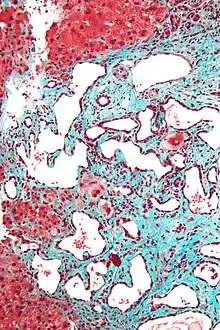

Histopathology of a bile duct hamartoma, high magnification, H&E stain. It shows typical features of bile duct hamartoma:

Micrograph of a bile duct hamartoma. Trichrome stain. Intermediate magnification

Micrograph of a bile duct hamartoma. Trichrome stain, high magnification

Low magnification micrograph of a bile duct hamartoma. Trichrome stain.